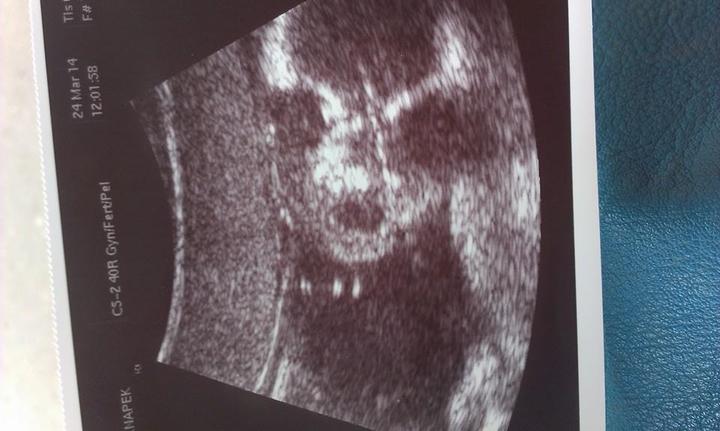

Když jsem procházela staré věci tak jsem našla tuhle fotku, i když s bývalým máme vztahy jaké máme, tahle fotka ve mě vzbuzuje hodně emocí. Nikdy v životě nezapomenu na celé těhotenství kdy se ke mě choval jak k princezně, hlavně nezapomenu na průběh porodu jak byl vyklepaný když jsem měla kontrakce po 3 minutách a on se na mě díval se strašným strachem a soucitem v očích když viděl jak mě to oblí a on mi nemohl nijak pomoct, taky si pamatuji jeho slova když jsem mu volala ať přijede do porodnice že du na sál, do té doby z něj byl hrdina jak se mnou půjde na sál, když jsem mu vynadala do telefonu tak radši zůstal na chodbě a čekal než to bude vše za mnou :D Po té co ho sestřička zavolala že může jít za námi a já ho viděla poprvé v životě plakat když držel naši úžasnou holčičku, nikdy jsem v jeho očích neviděla tolik pýchy, hrdosti, vděku a lásky.